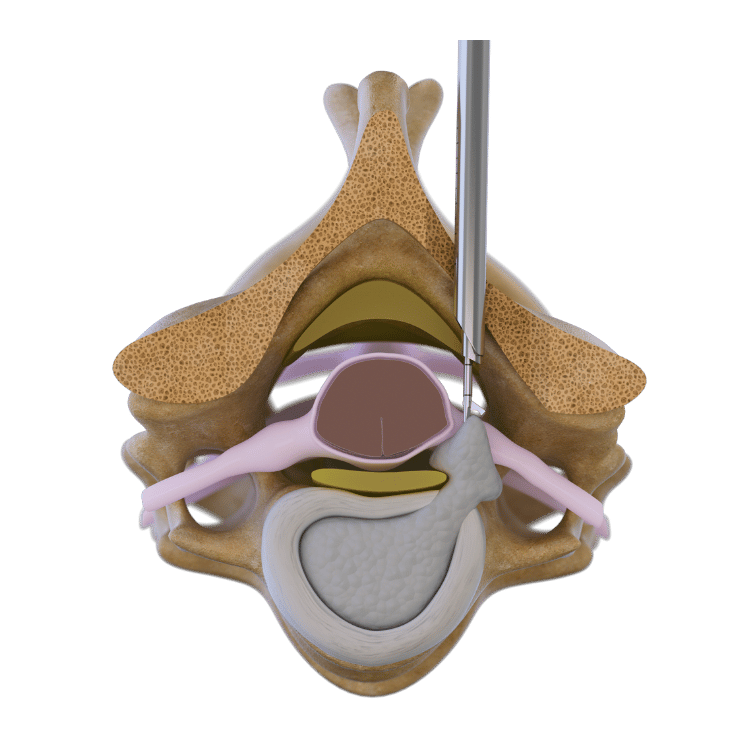

頸椎後方手術手技

完全内視鏡後方アプローチは、主に内外側から外側の椎間板ヘルニアに用いられます。この7 mm 径でのアクセスにより、非侵襲的に軟部組織を経て椎弓および椎間関節に到達できます。高解像度の内視鏡映像下で、電動バーで椎弓と椎間関節の一部を切除して椎間板ヘルニアの位置を特定し、それを除去して神経根の痛みを軽減します。

前方経椎間板手術法

このアプローチは、後方アプローチではアクセスできない、内側から内外側に限局した椎間板ヘルニアを治療します。腹側構造(食道、動脈など)を触診し、通過させた後、X線ガイド下で細いダイレーターを椎間板に挿入します。特殊な楕円形のダイレーターを頸椎椎間板の背側縁まで進めます。アクセススリーブを通して、内視鏡下で椎間板ヘルニアを経椎間板的に除去します。